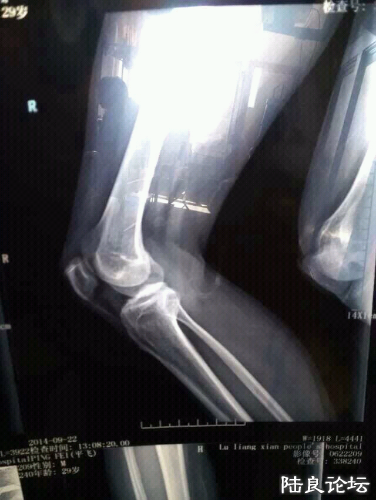

你爹临死前:死者为大,哪家不死人,我家送老人上山,下葬也犯法吗?9月22日,中午12点。曲靖市陆良县春光路!一不放鞭炮,二不敲锣打鼓,三不破坏环境,四不影响交通,一切都遵守了政府有关部门同意。凭什么伱们这么嚣张,谁给你们的权力,手持钢管不但把人打成重伤还用辣椒水喷酒群众,凡使用手机摄像的基本被抢夺砸坏,伤及无辜群众,几十人手持钢管殴打群众!)车也砸了,男女老少通打,还是人吗,这根恐怖分子有什么区别呢?看看这陆良政府有多腐败!他们是这样为人民服务的吗?还有天理吗?希望广大群众看到的转发,呼吁当时在场者拍下视频上传网上!看到的朋友帮忙扩散一下这些腐败份子!!!

如果真是这样,那这些执法人员太tm过分了。骨头都打断,真狠